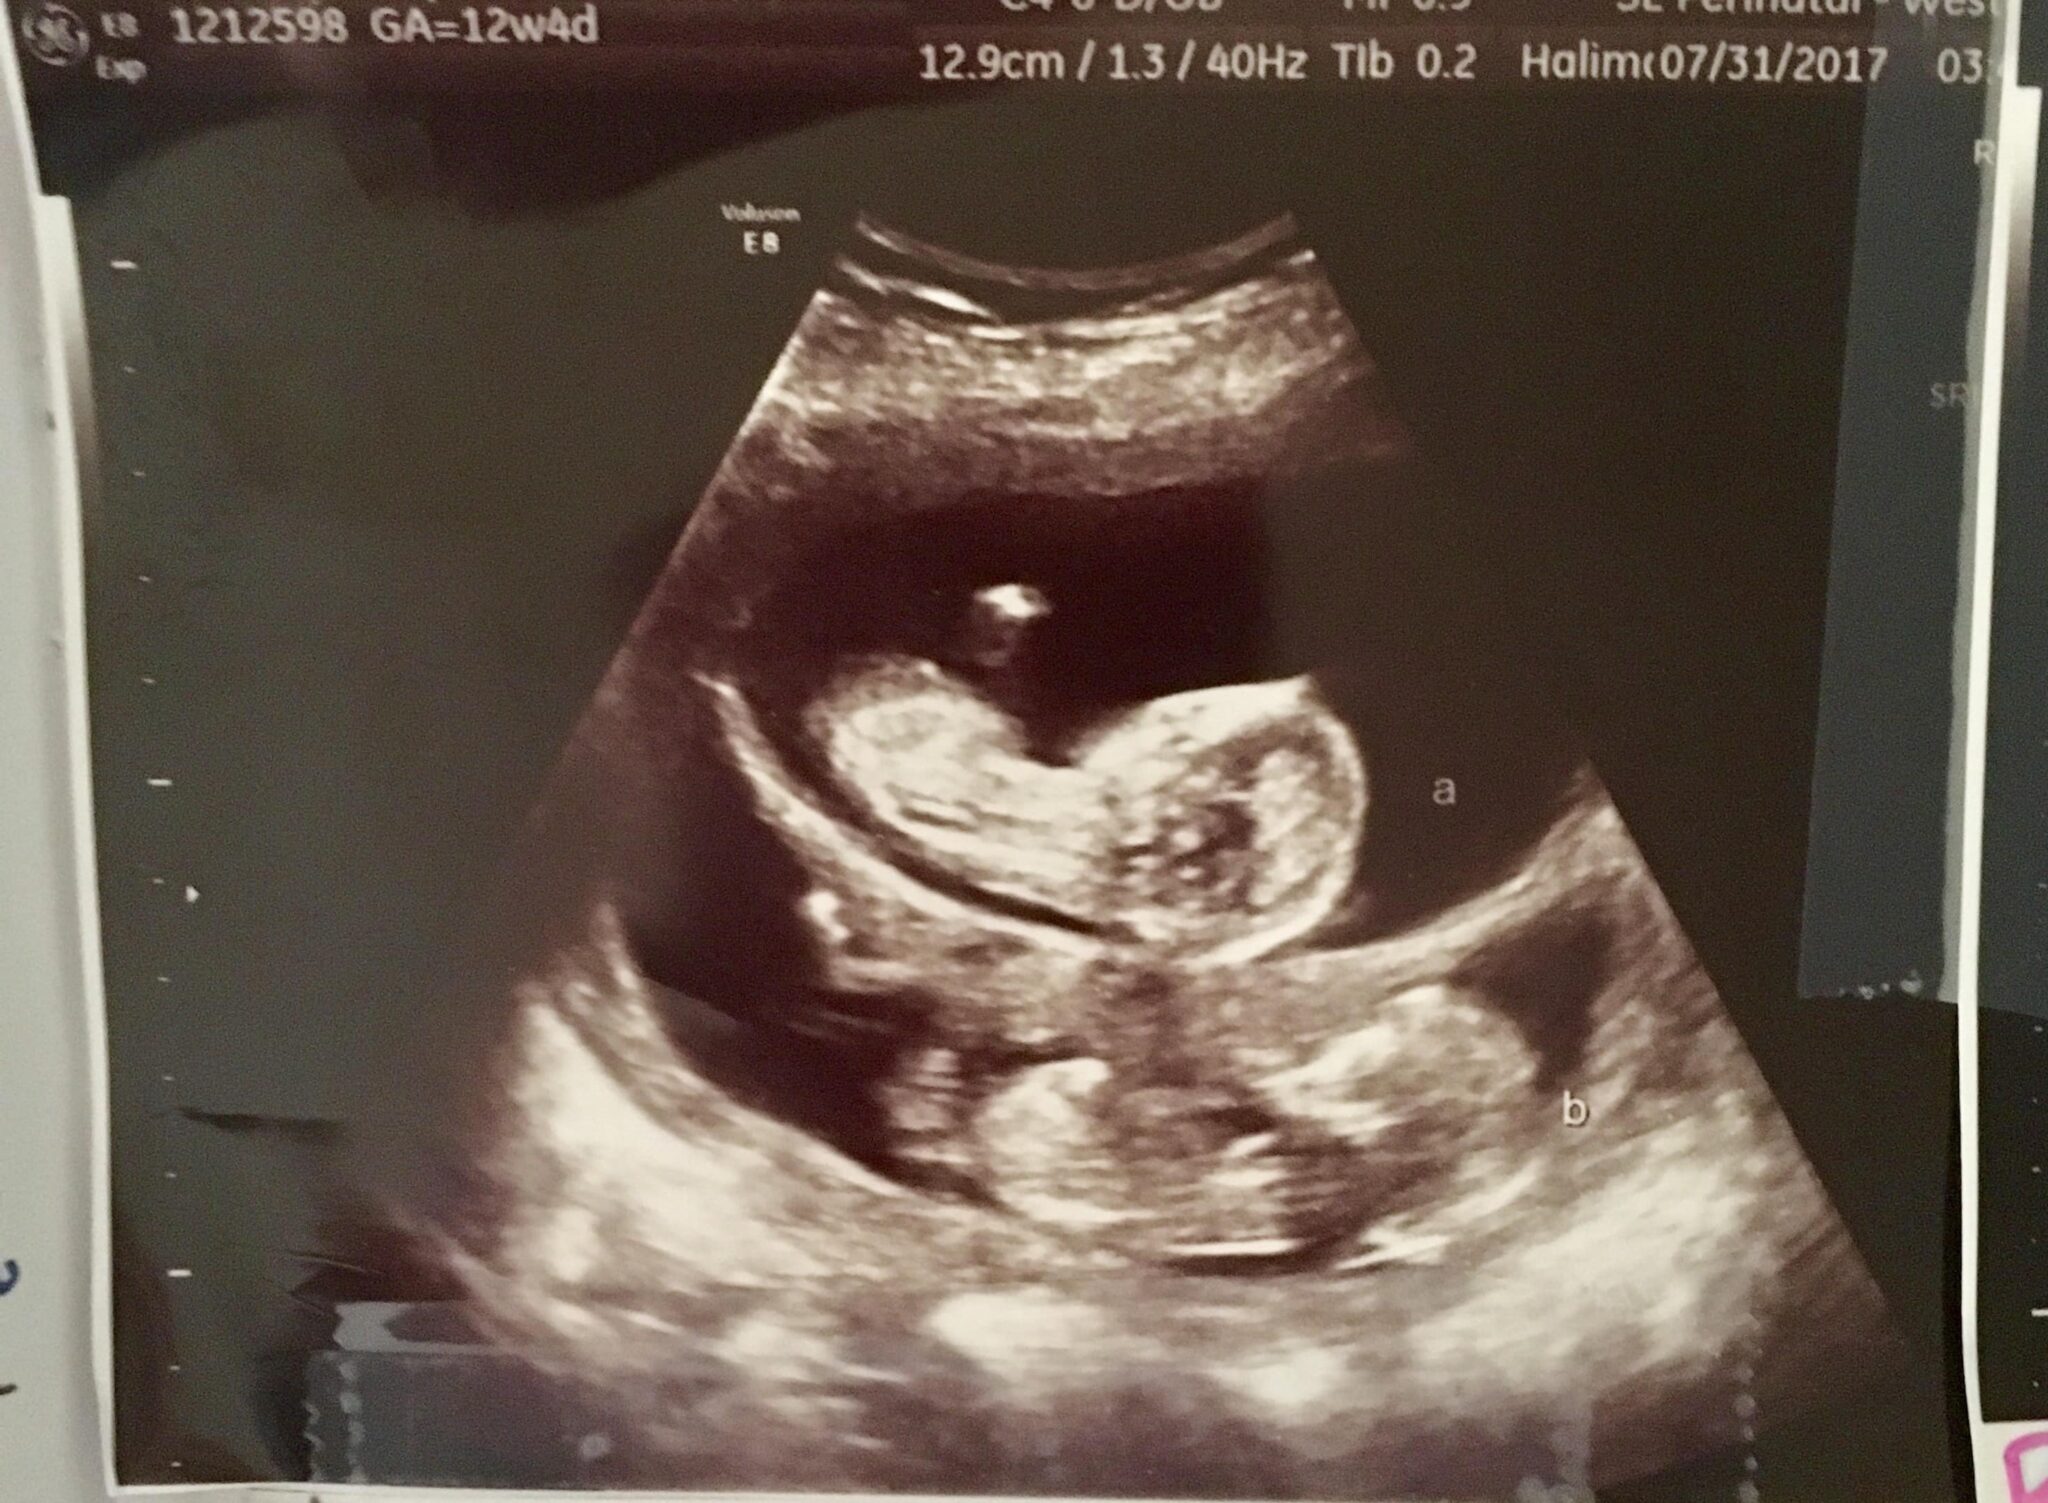

Ultrasound Photos at 12 Weeks Pregnant With Twins